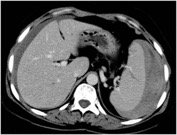

TC-22000, Hb-7.0 g/dl Pt-17sec, INR-1.45sec, Amylase- 115u/L. CT report was Grade IV splenic injury, Moderate Hemoperitoneum, Mild edema of the tail of pancreas, No bowel or other Visceral injury. As the patient was stable he was observed in the High dependency unit for 2 days with supportive medications and blood transfusions. His Hb improved up to 10.5 g/dl. He was then transferred to the room.